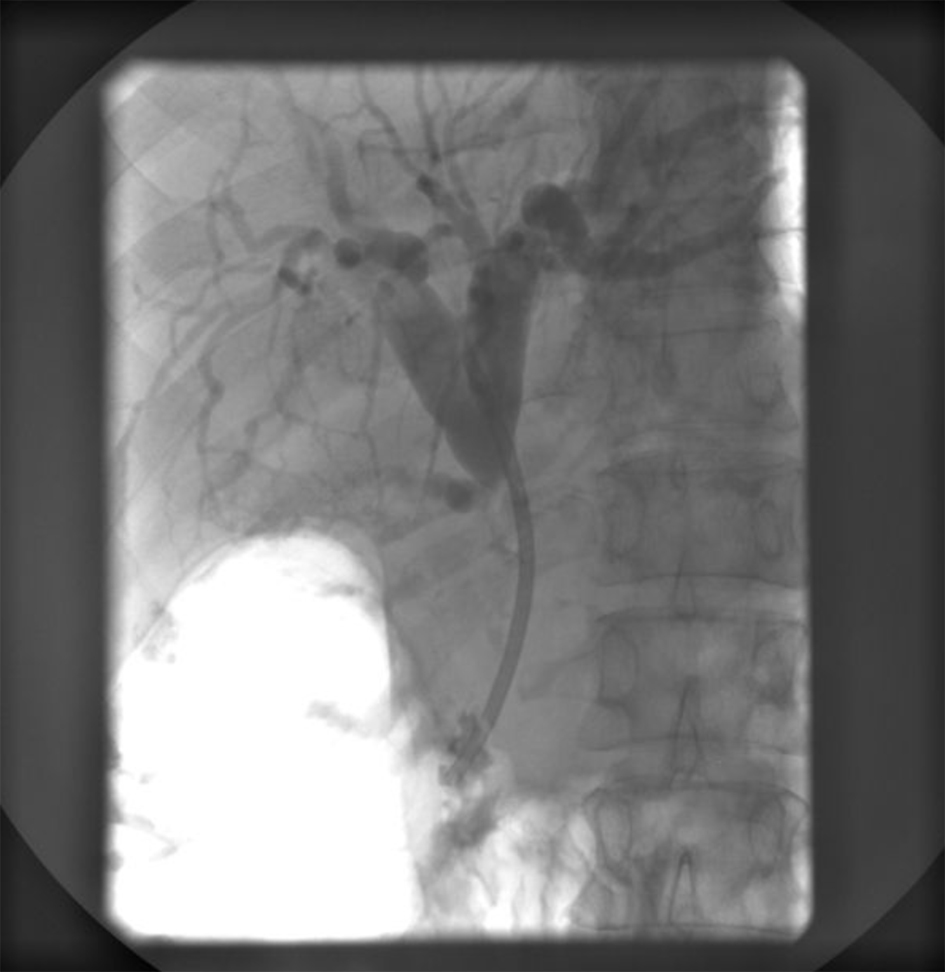

Endoscopic retrograde ERCP was made and showed a stenosis of common bile duct 3 cm in length with prestenotic dilatation of both left and right hepatic duct and intrahepatic bile ducts (Fig. 4). A papilotomy was then made, brush aspiration for cytological analysis and a biliary plastic stent (Amsterdam 10F, 6 cm) was inserted at the site of stenosis with good bile drainage (Fig. 5).

![]() Click for large image | Figure 5. ERCP showing an implanted plastic stent with adequate position in the common bile duct and appropriate function. |